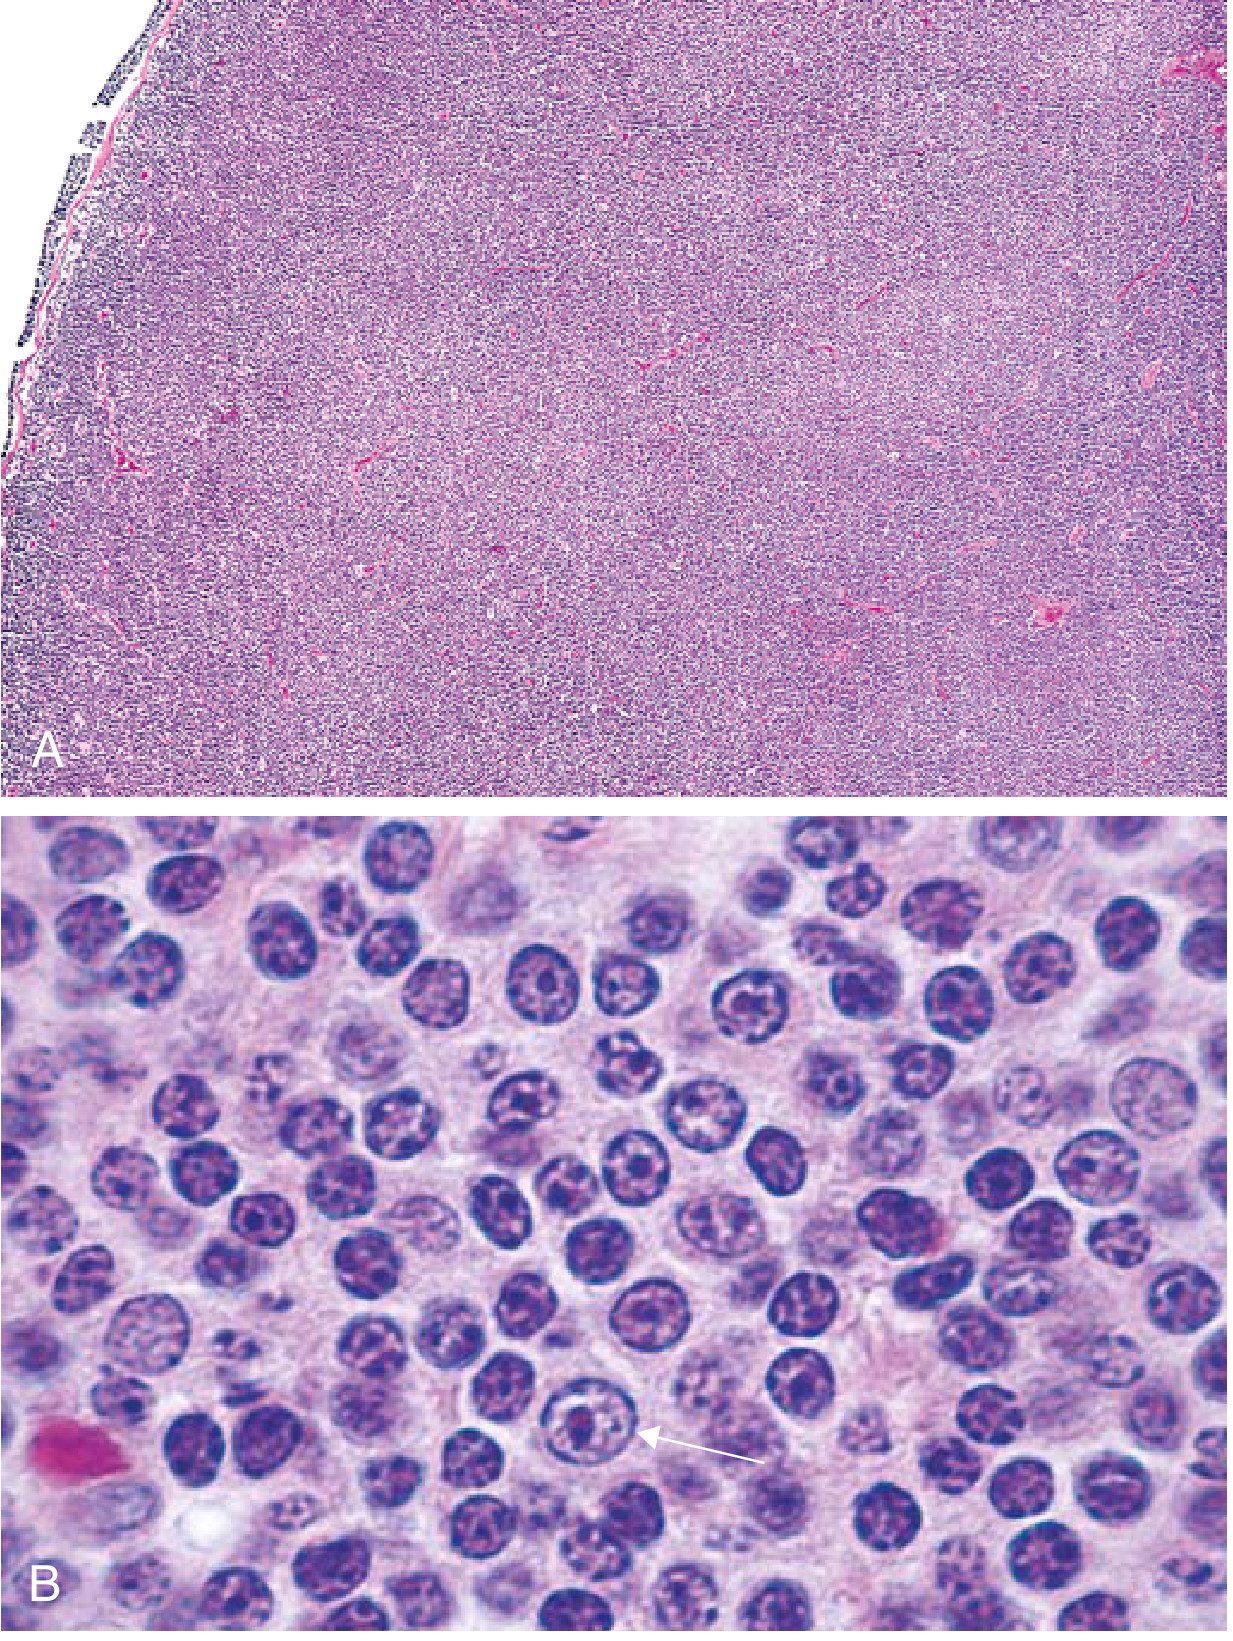

FIG. 10.20 — Follicular lymphoma. (A) Low power: distinctly nodular proliferation replacing the lymph node. (B) High power: centrocytes (small cleaved cells) mixed with centroblasts (larger cells with nucleoli).

FIG. 10.20 — Follicular lymphoma. (A) Nodular aggregates of lymphoma cells throughout the node. (B) Small cleaved centrocytes mixed with larger centroblasts; arrow indicates a prolymphocyte-like cell.

• Lymph nodes effaced by a distinctly nodular proliferation

• Predominantly centrocytes — slightly larger than resting lymphocytes with angular "cleaved" nuclei, coarse chromatin, indistinct nucleoli

• Mixed with variable centroblasts — larger cells with vesicular chromatin, several nucleoli

• Few mitoses, no apoptosis — distinguishes from follicular hyperplasia (where both are prominent)

• Occasional predominance of large cells = more aggressive histology

FIG. 10.22 — Burkitt lymphoma. Monotonous intermediate-sized cells with high mitotic activity and "starry sky" pattern from interspersed macrophages.

FIG. 10.22 — Burkitt lymphoma. Uniform intermediate-sized cells, high mitotic rate, and classic "starry sky" pattern.

• Intermediate-sized tumor cells with round/oval nuclei, 2–5 distinct nucleoli

• Moderate basophilic/amphophilic cytoplasm with lipid vacuoles (on smears)

• Very high proliferation AND apoptosis rates → tissue macrophages ingesting nuclear debris → "starry sky" pattern (macrophages = stars; dark tumor cells = sky)